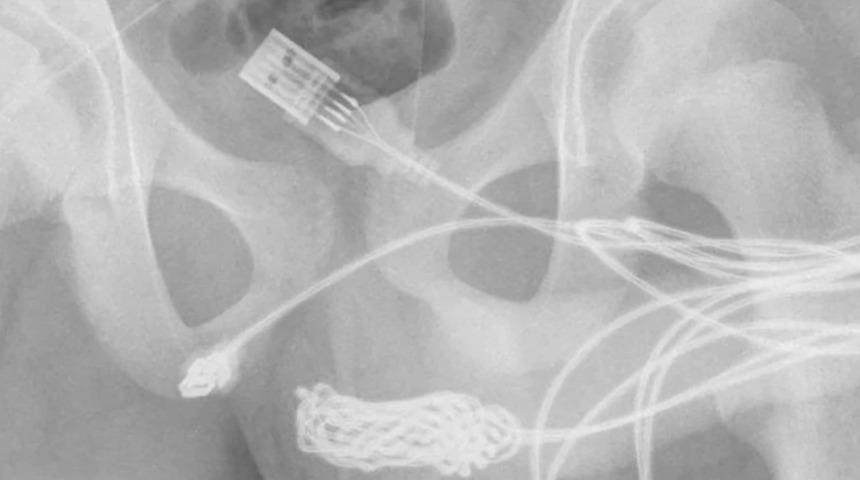

Rapora göre annesinin yanında utanan İngiliz doktorlara ayrı bir odada tüm durumu anlattı. Ameliyata alındı, cerrahlar cinsel organları ile anüsü arasındaki bölgede kesi yaparak kabloyu çıkardı.